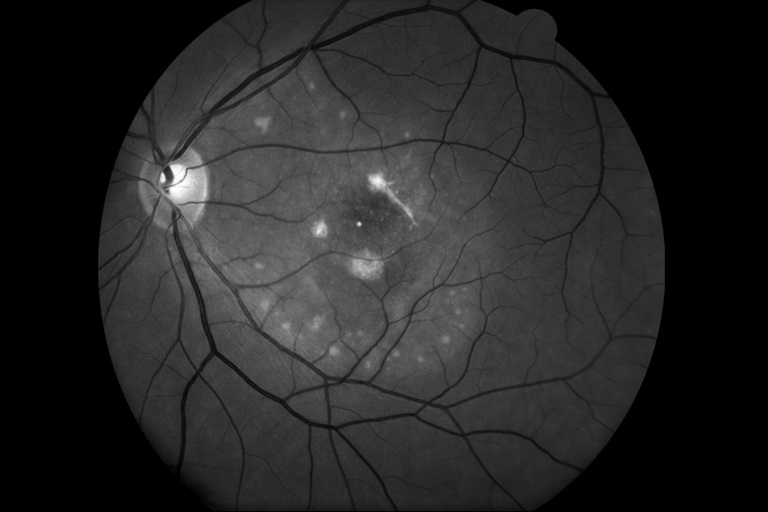

Best's Disease

Presented by Bradley Stern, BA, CRA, OCT-CThis photograph received Honorable Mention in the category "Monochromatic Photography" and was displayed at the 2024 ASCRS/OPS Society Exhibit.